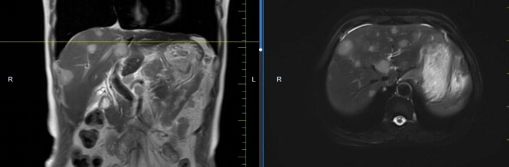

患者孟某某,女,73歲,因腹部不適行胃鏡及PET-CT,發(fā)現(xiàn)胃癌、骨、肺、肝多發(fā)轉移,胃壁厚約2cm,腹腔大淋巴結約3cm,肝最大轉移灶約3cm。同樣6周期化療+免疫,聯(lián)合中醫(yī)中藥后病灶明顯縮小,現(xiàn)已進入維持治療階段,身體狀況恢復至常人水平。

治療前

治療后